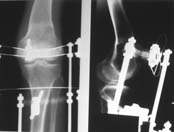

Пациент В. 53 лет, травма в феврале 2009. ДЗ. Открытый оскольчатый перелом нижней трети голени. При боли поступлении выполено ПХО, аппарат Илизарова. В последующем проводили ВХО, резекция костных отломков, укорочение 6 см, рана зажила. Была выполнена остеотомия большеберцовой кости в проксимальном отделе, резекция. Производилось тракция. На последних рентгенограммах выявлено, что одновременно с "выращиванием" регенерата произошло низведение надколенника на длину выращенного регенерата. Клинически: активное разгибание сохранено, объем движений в колене 180-110 градусов. Черными стрелками обозначен верхний край надколенника с одной и с другой стороны. Красная стрелка обозначает пальпируемую связку надколенника. Причина - остеотомия выше места прикрепления связки надколенника. Вопрос: была ли у кого подобная ситуация? Что делать? При первом обдумывании приходит решение: отсечение места прикрепления связки надколенника с костным блоком, перемещение на "правильное" место, укорочение сухожилия четырехглавой мышцы.

По снимкам - плотность регенерата хорошая, сложностей с фиксацией в него костного "основания" быть не должно.

К сожалению, подобное осложнение "нет-нет да и возникает" при удлинении, коррекции деформации голени. В англоязычной литературе оно описано как "patella baja". Один из вариантов лечения - проксимальное перемещение надколенника приемами чрескостного остеосинтеза.